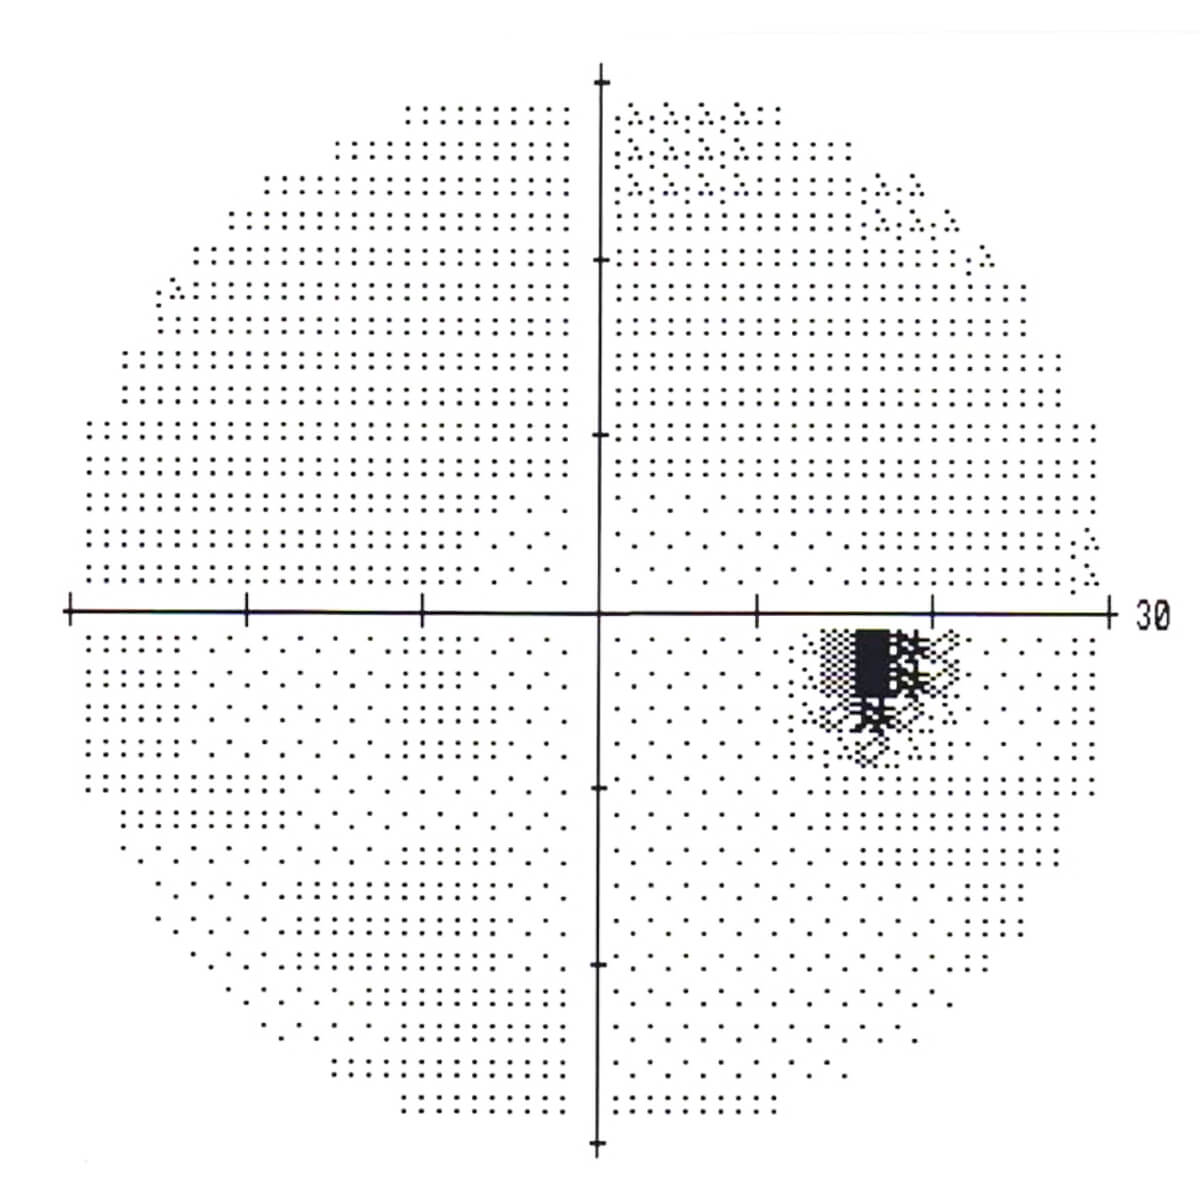

視野検査 正常

黒い部分は視神経乳頭のところで、マリオット盲点と呼びます。